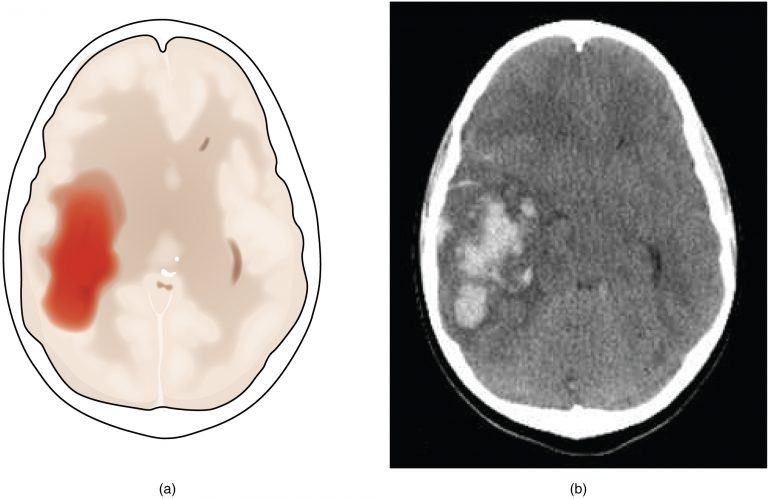

L'emorragia cerebrale consiste nella rottura di un vaso sanguigno (normalmente un'arteria) che provoca sanguinamento sia dentro che intorno al cervello. L'emorragia cerebrale è una perdita di sangue all'interno del cervello, con versamento ematico nei tessuti che lo compongono. Ora è ricoverata in ospedale, non ha avuto conseguenze dal punto di vista motorio né neurologico. L'emorragia cerebrale (in inglese conosciuta come intracranial hemorrhage, intracranial bleed o ich), corrisponde ad una fuoriuscita più o meno abbondante di sangue da un vaso arterioso o venoso. Il emorragia cerebrale è un termine generico per tre diverse emorragie, che possono verificarsi nell'area del cranio e del cervello. Ciò le ha portato ad avere una emorragia cerebrale di 4 cm. Le emorragie che interessano il tessuto cerebrale si chiamano: Si distinguono emorragie cerebrali a sede tipica, localizzate cioè nelle strutture profonde.

Si distinguono emorragie cerebrali a sede tipica, localizzate cioè nelle strutture profonde. Ruolo della neuroradiologia nell'emorragia cerebrale. Nonostante un'apparente stabilità dell'incidenza in questi. L'emorragia cerebrale (in inglese conosciuta come intracranial hemorrhage, intracranial bleed o ich), corrisponde ad una fuoriuscita più o meno abbondante di sangue da un vaso arterioso o venoso. Cefalea (improvvisa e molto violenta).

L'emorragia cerebrale è una condizione neurologica causata dalla rottura di un'arteria con conseguente sanguinamento all'interno del cervello stesso. Il neuroradiologo è una figura peculiare che si innesta, in generale, nel percorso diagnostico terapeu Anche emorragie a sede atipica. Le emorragie che interessano il tessuto cerebrale si chiamano: È causata dalla rottura di un'emorragia cerebrale è etichettata a seconda del punto dove si verifica: L'emorragia cerebrale è una sindrome neurologica acuta dovuta alla rottura di un vaso arterioso cerebrale e al conseguente stravaso di sangue nel parenchima cerebrale. L'emorragia cerebrale è una fuoriuscita più o meno copiosa di sangue da un vaso arterioso o venoso, frequentemente sclerotico, dell'encefalo. L'emorragia cerebrale è una perdita di sangue all'interno del cervello, con versamento ematico nei tessuti che lo compongono.